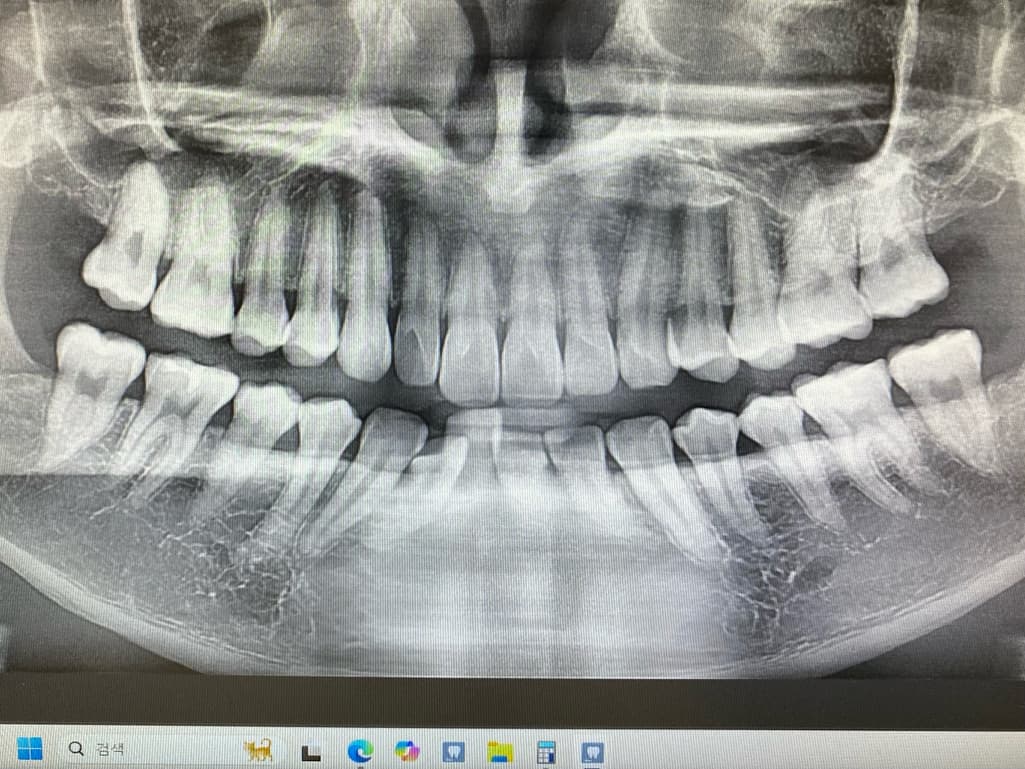

1치과는 충치가 있는 것 같다 양 옆 색상 차이가 있다 눈으로 확인 되는 정도라면 치료 해야 할 시기이다

위치 왼쪽 위 2번째 어금니 치료 한 부위 2차 충치

왼쪽 위 4번째와 3번째 사이 인접면 충치

2치과는 엑스레이로 찍어보고 육안으로 봐도

치료할 정도는 아니고 성인이니 검진 주기를 짧게 해서경과를 지켜보자

3치과는 엑스레이와 육안검사 확대 엑스레이 까지

찍었지만 너무 작다 자신들이 치료하는 기준에

미치지 못해서 치료하지 않고 경과를 지켜보자

사진에 보이는 정도면 충치가 안쪽에 많이 진행됫을 가능성이 있습니다. 저라면 인레이로 치료를 할것같습니다.

육안으로 보였을 경우 인절면에 충치가 있는 것으로 보입니다. 하지만 방사선상에는 크게 보이진 않습니다. 눈으로 보이는 충치가 있기 때문에 인접면 충치는 치료를 하는 것이 좋을 것으로 생각됩니다.

레진보다는 인레이를 하는 것이 일반적이며 레진은 술자를 잘 선택하셔야 합니다. 치료는 필요해보입니다.